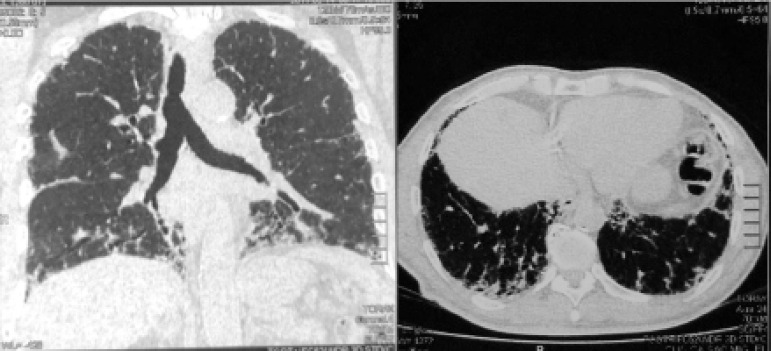

High resolution computed tomography (HRCT) of the chest demonstrated numerous parenchymal bands, bilateral honeycomb images, and diffuse air trapping, pattern compatible with fibrotic HP (Figure 1). Spirometry findings revealed a severe restrictive pattern. Forced vital capacity was 1.5 L (41% of expected), and forced expiratory volume in the first second was 1.41 L (50% of expected). Extended investigation included diffusing capacity of the lung for carbon monoxide of 43%. After a multidisciplinary discussion and the need for a definitive diagnosis, which could even have implications related to this patient’s work activity, surgical lung biopsy was indicated. It confirmed the presence of interstitial pneumonia with a bronchiolocentric distribution, old fibrosis areas and cholesterol crystals foci surrounded by giant cells, typical pattern for fibrotic HP (Figure 2). By associating exposure with radiological and histopathological changes, the final conclusion was chronic PH. Considering the ongoing inflammation process, an optimized inhaled dose of corticosteroid was prescribed. Endoscopy indicated no abnormalities. A 24-hour esophageal pH test was indicated as differential diagnosis for gastroesophageal reflux disease, despite the absence of pyrosis and dyspepsia. By the end of consultation, we explained the disease process to the patient, as well as his prognosis, the importance of preventive measures such as influenza and pneumonia vaccinations, and the risks of a new pesticide exposure.

Figure 1.

High resolution computed tomography of the chest demonstrating numerous parenchymal bands, bilateral honeycomb images and diffuse air trapping.